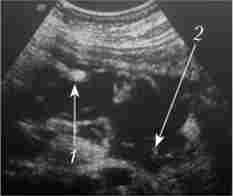

Мал. 28.5. Абсцес сальникової сумки і секвестри:

1 - сальниковая сумка; 2 - секвестру

Різниця між ультразвукової картиною абсцесу і гематоми черевної порожнини полягає в наявності або відсутності капсули. Гематома нс обмежена капсулою, її вміст неоднорідне, часто містить згустки, іноді в порожнині гематоми можна візуалізувати ток рідини. Ультразвукова картина абсцесів і гематом черевної порожнини різної локалізації досить характерна. Поддіафрагмальние рідинні скупчення мають серповидную форму, абсцеси сальникової сумки - неправильну форму або довгасту (овоидную) форму (рис. 28.5).